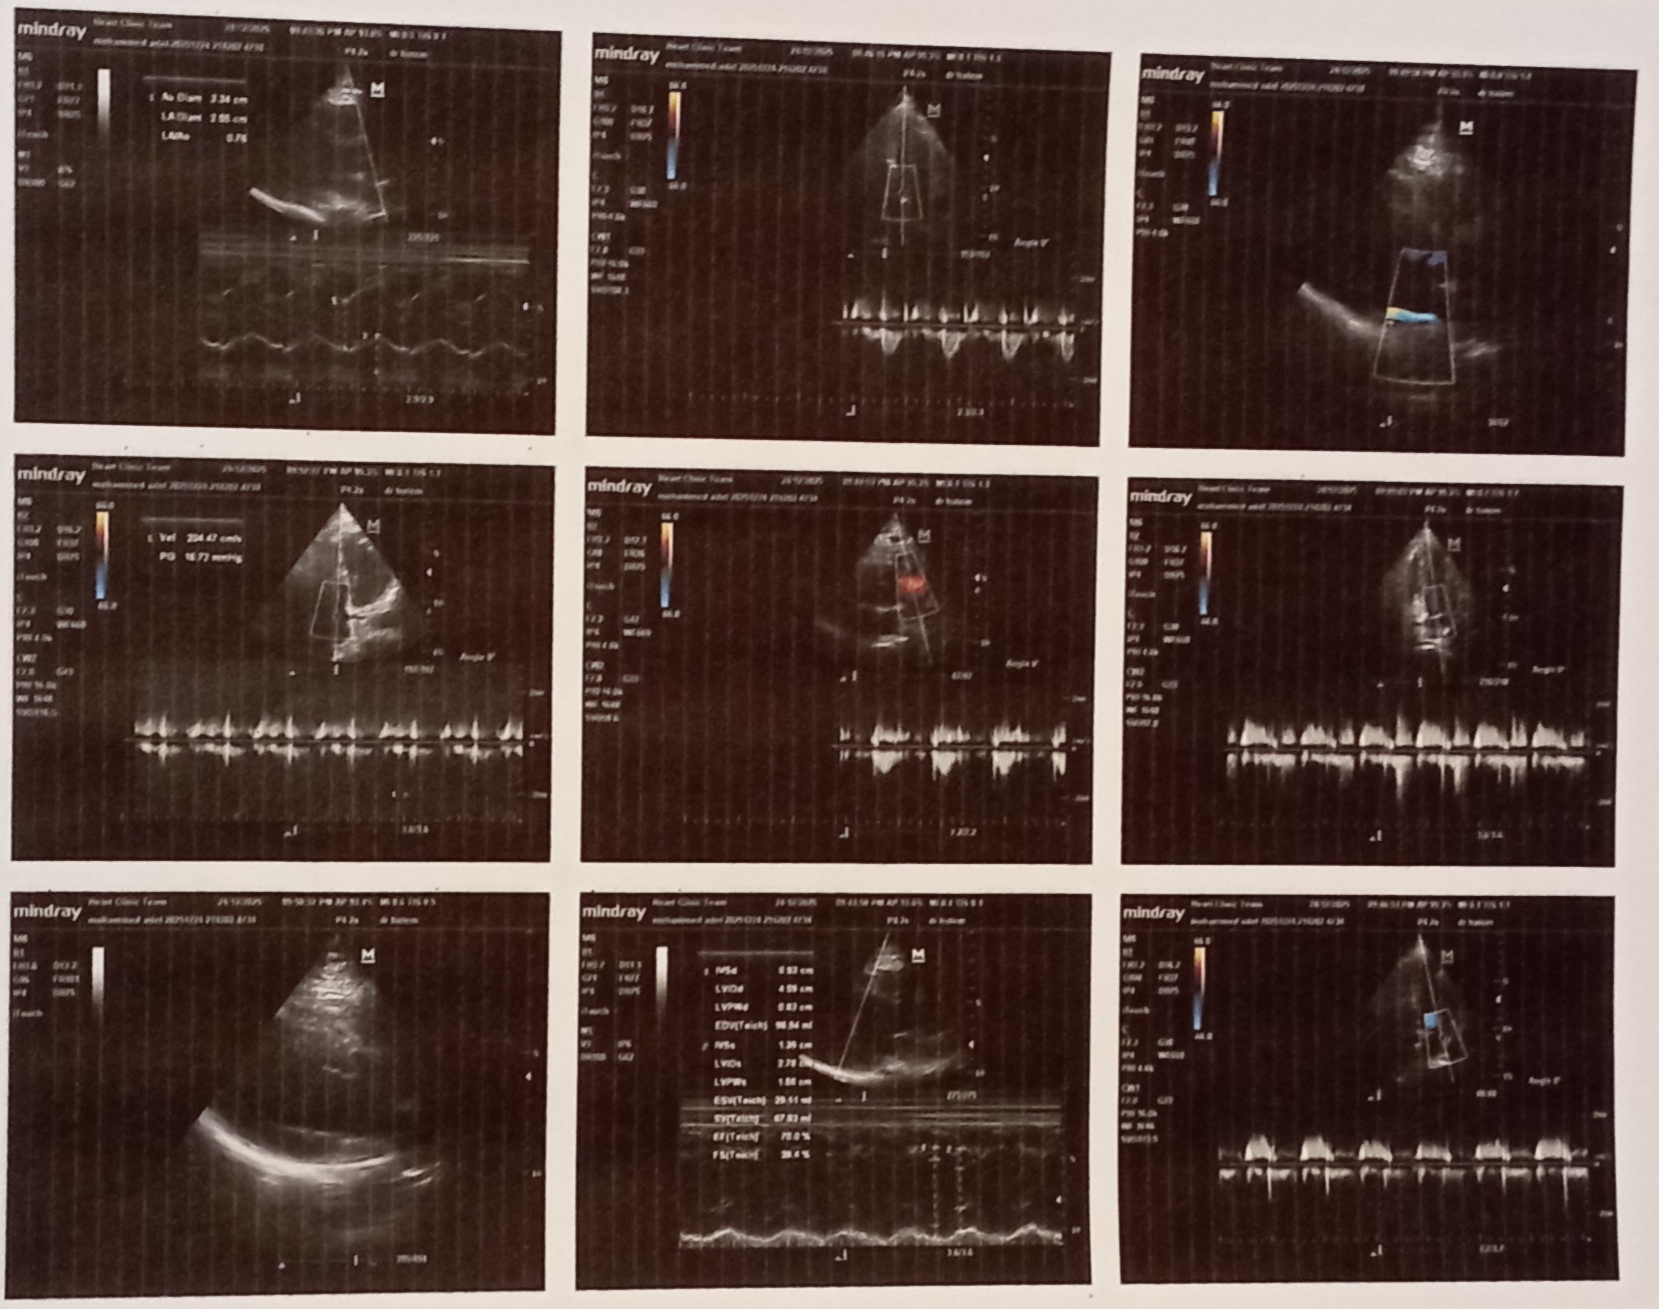

عندى ساعات ضربات قلب سريعة ولما رحت لدكتور قلب وعملت ايكو قالى انت عندك ارتجاع بسيط غير مركزى فى الصمام الميترالى وباخد كونكور 2.5 هل فى علاج للموضوع ده مع ان انا عديت شهرين والموضوع لسة زى ماهو ، اعمل ايه وهل فى مضاعفات لموضوع الارتجاع ده مع انى عامل ايكو ورسم قلب ياريت دكتور استشارى قلب موجود هنا يفيدنى.

عندى ساعات ضربات قلب سريعة ولما رحت لدكتور قلب وعملت ايكو قالى انت عندك ارتجاع بسيط غير مركزى فى الصمام الميترالى وباخد كونكور 2.5 هل فى علاج للموضوع ده مع ان انا عديت شهرين والموضوع لسة زى ماهو ، اعمل ايه وهل فى مضاعفات لموضوع الارتجاع ده